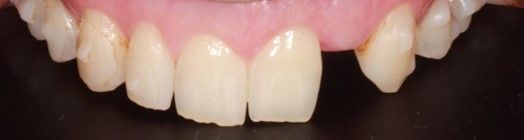

Se presenta un paciente varón de 34 años de edad, no fumador y sin antecedentes médico-quirúrgicos de interés (ASA I), que acudió a la consulta demandando una mejora en la estética de su sonrisa.

El paciente presentaba una agenesia congénita en el incisivo lateral superior izquierdo que había sido tratada previamente con ortodoncia para cerrar dicho espacio.

Tras el examen intraoral del paciente y el estudio radiográfico, se plantea la opción de tratamiento de abrir nuevamente el espacio mediante ortodoncia para rehabilitar la ausencia con un implante de circona, asegurando la estética que demandaba el paciente.